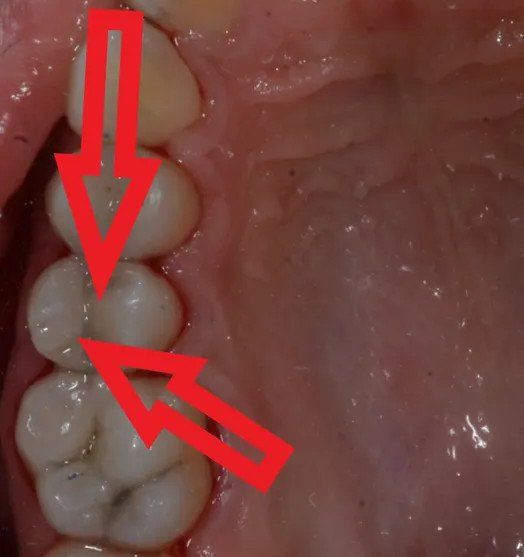

Viene presentato un caso in cui si evidenzia la presenza di carie mesiale e distale su un 25 (secondo premolare superiore di destra) attraverso l'analisi radiografica. Si deve sottolineare la difficoltà di metterne in risalto e di determinarne l'estensione solo mediante la radiografia. Nella fotografia successiva, l'entità e l'estensione della carie appaiono notevolmente superiori a quanto potesse essere dedotto dalla sola radiografia. Si mostra poi la cavità ripulita dalla carie, evidenziando la perdita di tessuto dentale causata da essa. Infine, si presenta l'otturazione appena completata, con i segni della cartina da articolazione ancora visibili, utilizzata per verificare l'altezza della cura, che richiederà successivamente un ulteriore rifinitura e lucidatura.